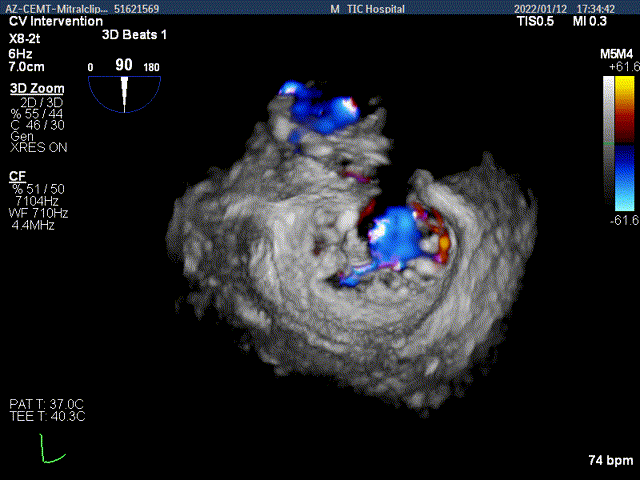

3D-color-VIEW验证残余返流来源

抓捕内侧残余脱垂,color-view示残余返流逐渐减少,主要来源于两个夹子之间

3D-Color-view验证微少量残余返流